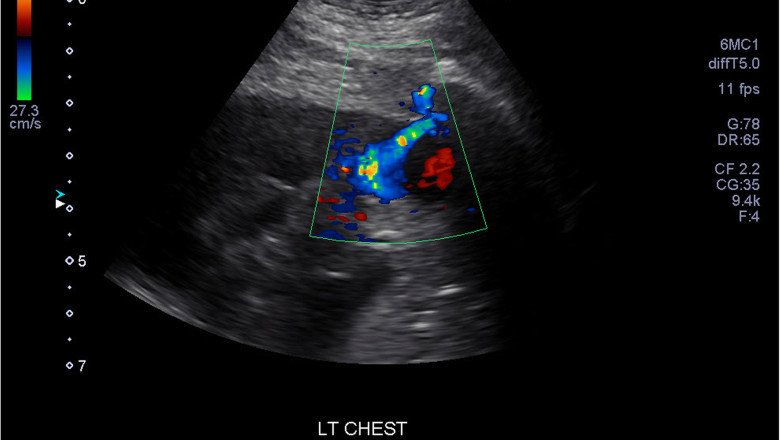

Doppler Ultrasound

A Doppler Ultrasound is a noninvasive diagnostic that uses circulating red blood cells to reflect high-frequency sound waves (ultrasound) to assess the blood flow via your blood arteries. Normal ultrasounds employ sound waves to create images, but they are unable to depict blood flow.

Many conditions can be identified with a Doppler ultrasonography, including:

·       Clots of blood

·       faulty valves in your leg veins may result in blood or other fluids pooling in your legs (venous insufficiency)

·       Congenital heart illness and heart valve abnormalities

·       an obstructed artery (arterial occlusion)

·       diminished blood flow to your legs (peripheral artery disease)

·       enlarged arteries (aneurysms)

·       arterial narrowing, such as in your neck's arteries (carotid artery stenosis)